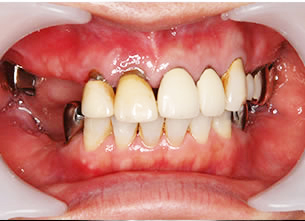

症例1 : 上下顎無菌顎症例

69歳、男性。

• 上顎は両側サイナスリフトと同時に即時荷重を行った。

• 下顎は抜歯即時埋入即時荷重を行った。

• 最終補綴物は、チタンのP.I.B.とM.B.のコンビネーションで修復した。

• 本症例の要旨は第39回日本口腔インプラント学会(大阪)にて症例報告した。